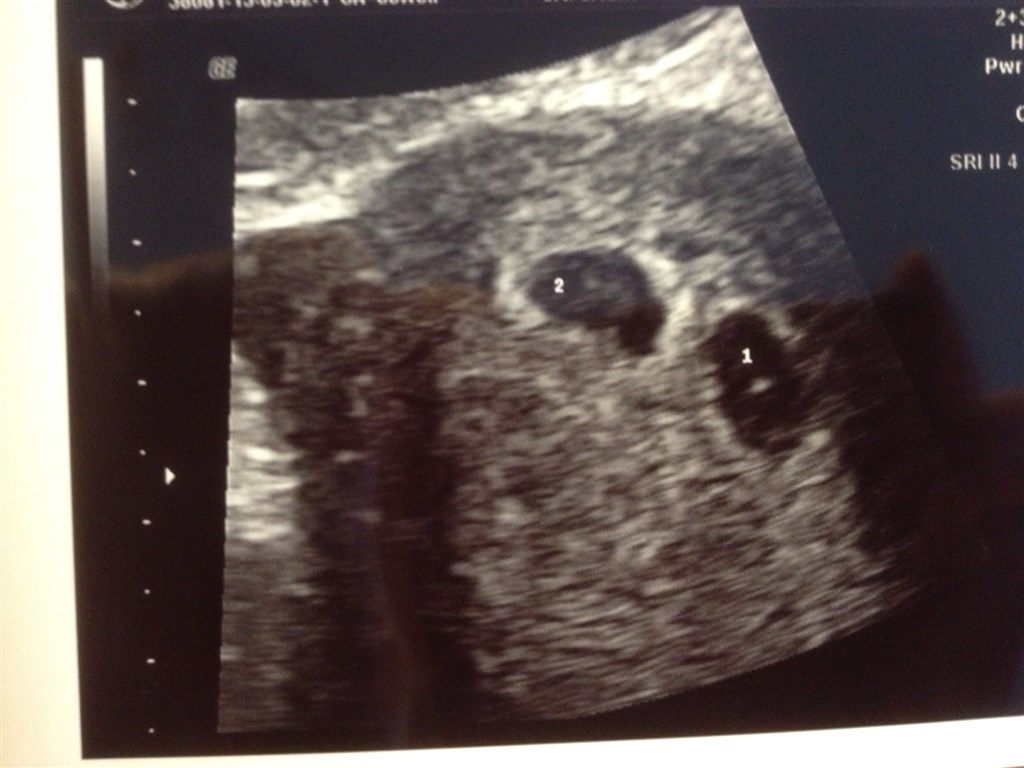

Vi er lige kommet hjem med en skumfidus i maven med et fint hoppende hjerte

Det er så fantastisk, men samtidig også så svært at forstå at det endelig er sket. Er så lykkelig

Vedhæftede fotos (klik for at se i fuld størrelse)